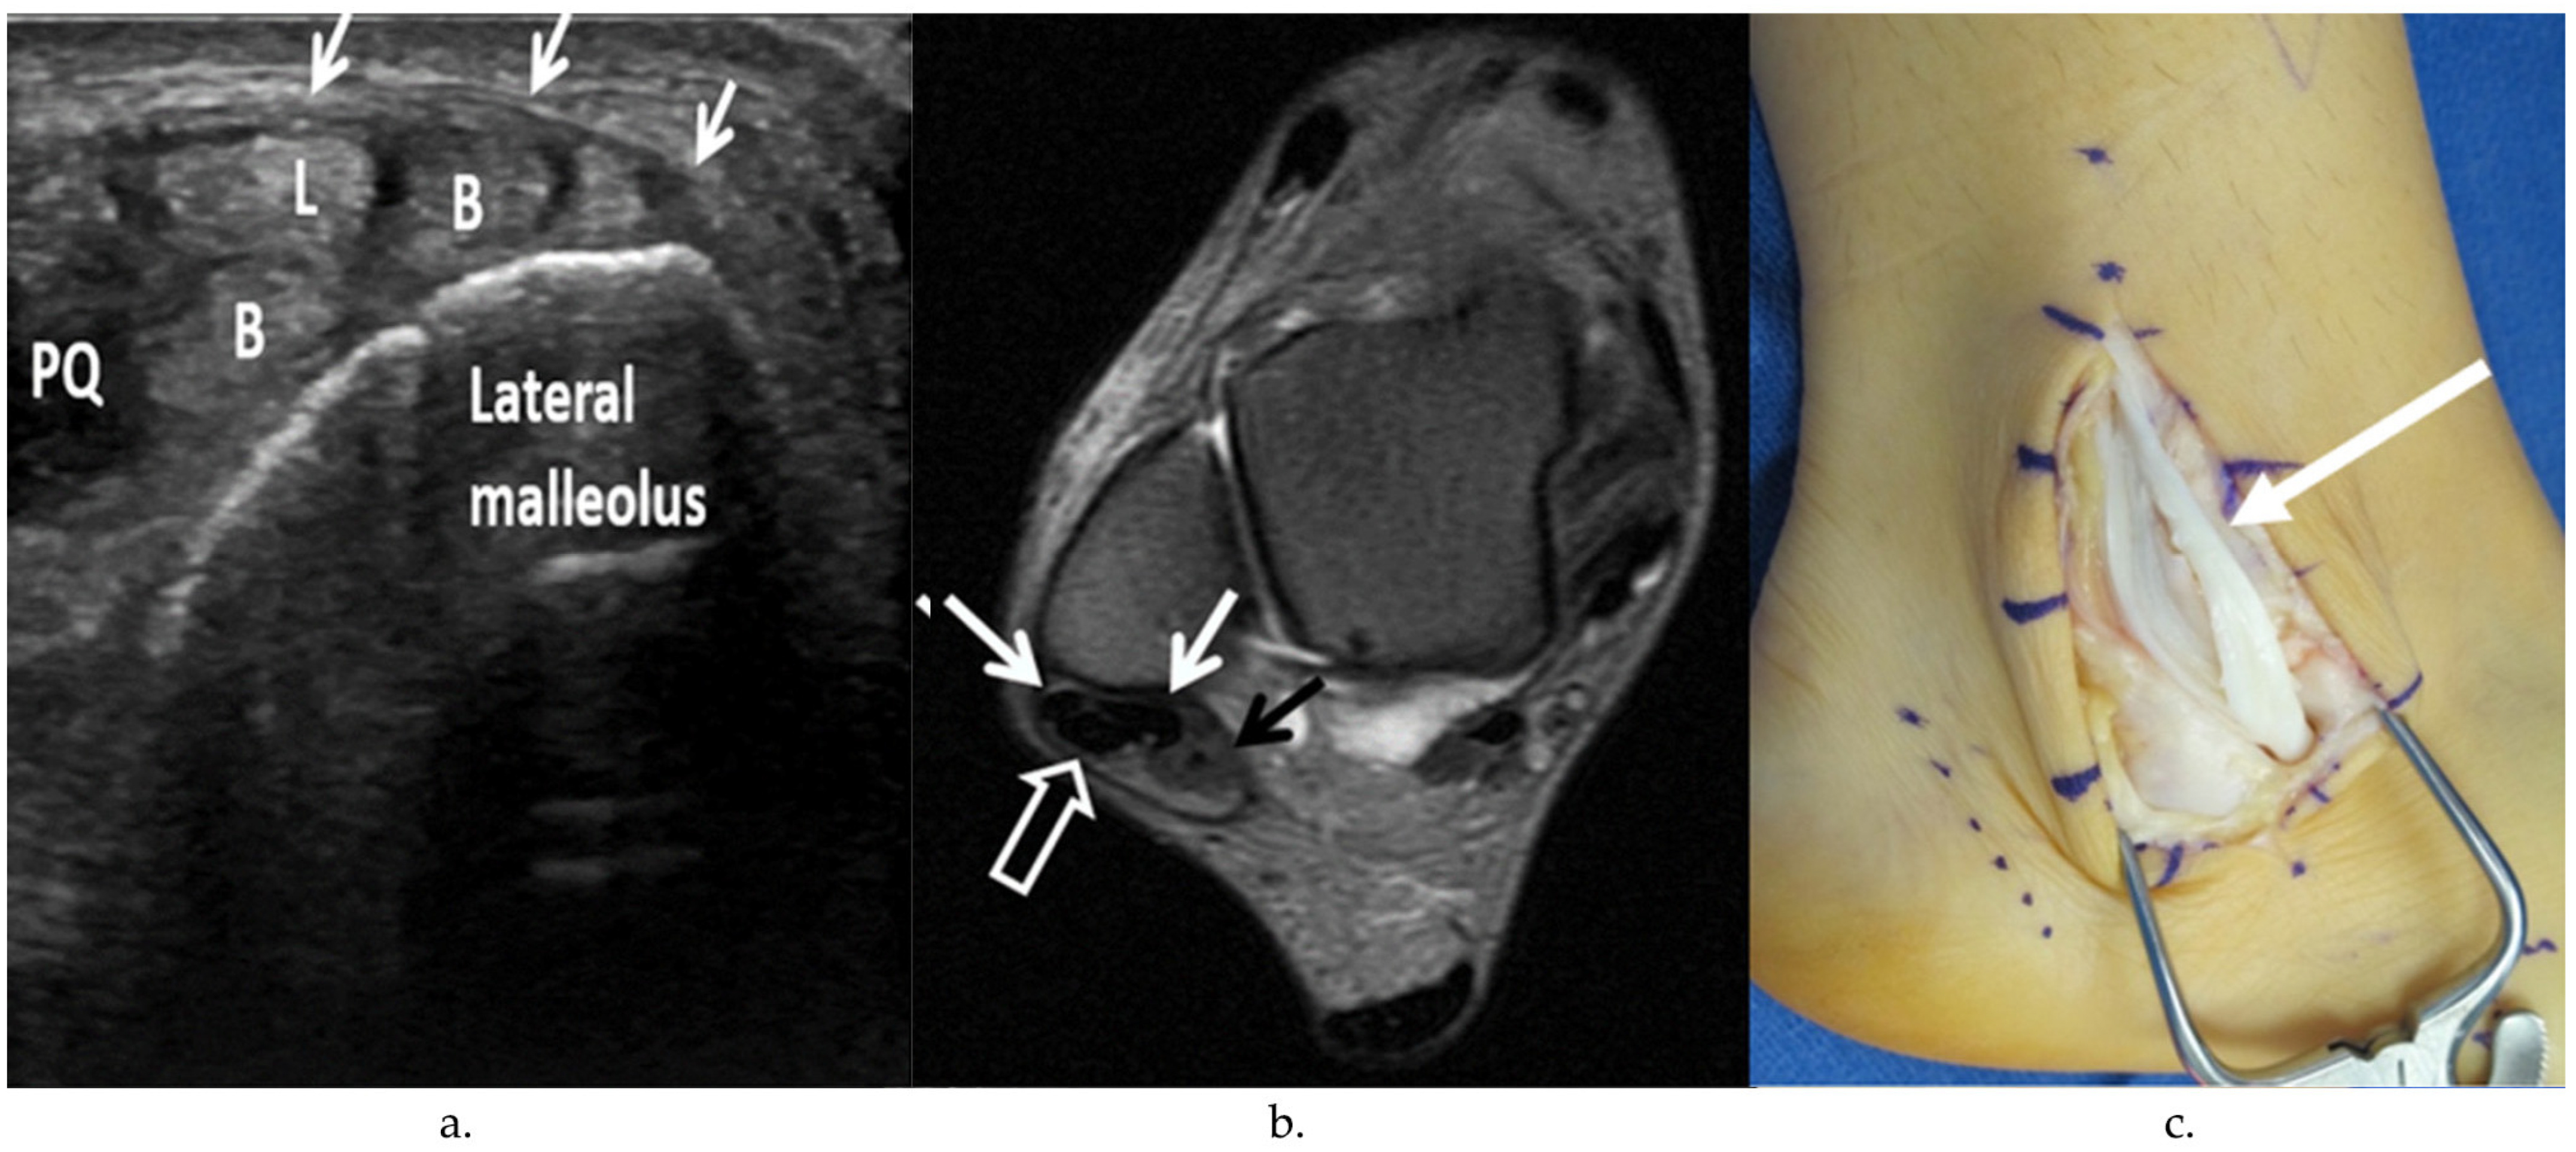

4.1. Peroneus Brevis Tear